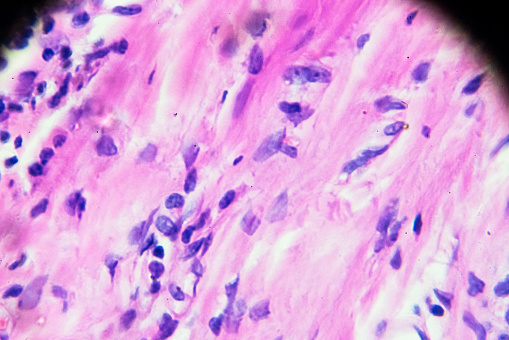

Lo + visto de la semana en MedlinePlus en español: Enfermedad de Hodgkin ow.ly/M6k750xeJcZ